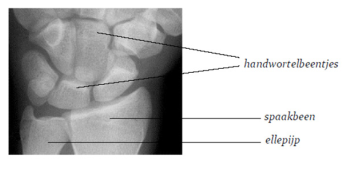

Je pols

Je pols is een gewricht. Het wordt gemaakt door de botjes in je hand en de twee botten in je onderarm: je spaakbeen en je ellepijp. Bij kinderen is het bot veel soepeler dan bij volwassenen. Om het bot zit een laagje dat beenvlies heet. Bij jou is dit laagje dikker dan bij volwassenen.